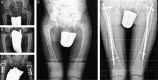

Background: In children, intramedullary nailing (IN) has been proposed as the best treatment when the femur and tibia are totally affected by fibrous dysplasia (FD). However, in younger children IN must be repeated to maintain stabilization of the affected skeletal segment during growth. We report the long-term results in a cohort of patients in whom more than two-thirds of cases had IN repeated during growth.

Methods: Twenty-nine femurs and 14 tibias totally affected by FD were treated by IN in 21 patients with polyostotic FD and McCune-Albright syndrome. Thirteen patients with 35 femoral and tibial deformities had a painful limp whereas 8 presented fractures. The patients had their first IN at a mean age of 9.26±2.68 years (range: 4 to 14 y). IN was repeated during growth in the younger patients, and all the patients underwent a mean of 2.13 femoral and 1.50 tibial IN per limb. The last IN was performed at a mean age of 16.42±1.95 years (range: 11 to 19 y). Titanium elastic nails and adult humeral nails were used in younger children, whereas adult femoral cervicodiaphyseal and interlocking tibial nails were used in older children and adolescents. At the latest follow-up, the patients were evaluated with a clinicoradiographic scale. All the data were statistically analyzed.

Results: The mean length of follow-up from the last IN was 6.47±3.10 years (range: 3 to 14 y), and the mean age of the patients at follow-up was 22.85±3.53 years (range: 14 to 29 y) when lower limbs were fully grown in all but 1 patient. Satisfactory long-term results were obtained in about 81% of our patients, while complications occurred in 32.5% of the 43 cases.

Conclusion: Lower limb IN-that was repeated in younger children during growth-provided satisfactory long-term results in most of our patients, with fracture and deformity prevention and pain control, regardless of the high rate of complications that mainly affected the femoral cases. Missing scheduled follow-ups was the main predictor of a poor result.